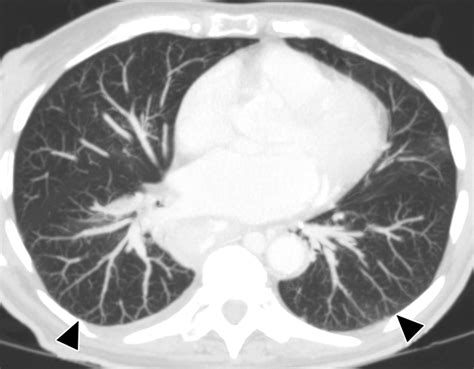

The Impact of Pulmonary Conditions on the Heart

There is a strong “heart-lung” connection that cannot be ignored. Chronic obstructive pulmonary disease (COPD) and other lung disorders often cause hypoxia (low oxygen levels). The body reacts to low oxygen by constricting pulmonary blood vessels, which increases pulmonary artery pressure. Over time, this chronic strain leads to a condition known as cor pulmonale, where the right ventricle becomes enlarged and eventually fails to keep up with the demands of the body.